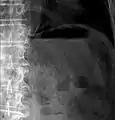

Pneumatosis intestinalis at computed tomography in intestinal ischemia. Lung window for better representation of the gas deposits in the intestinal walls. Coronal reconstruction.

Pneumatosis intestinalis in computed tomography with intestinal ischemia. Lung window for better representation of the gas deposits in the intestinal walls.